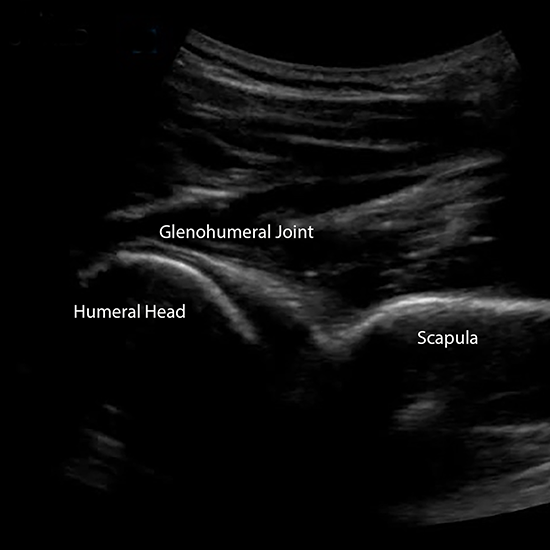

A shoulder ultrasound is a procedure that employs ultrasonic imaging to assess the rotator cuff and the soft tissues surrounding it. A rotator cuff is a group of muscles and tendons that work together to stabilise the shoulder joint. It is the most commonly requested ultrasound exam and provides a dynamic assessment of the shoulder.

Shoulder ultrasound, which uses sound wave technology rather than radiation, can be very effective in diagnosing cases of shoulder impingement, instability, and rotator cuff disorders such as muscular, tendon, and ligament damage, bursitis, and joint effusion (swelling).

The Ultrasound Shoulder Test detects unexplained shoulder pain, swelling, and infection. The doctor may order this test to be performed on you.